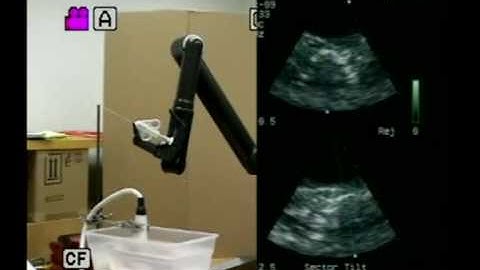

Toward Real-time 3D Ultrasound Registration-based Visual Servoing for Interventional Navigation